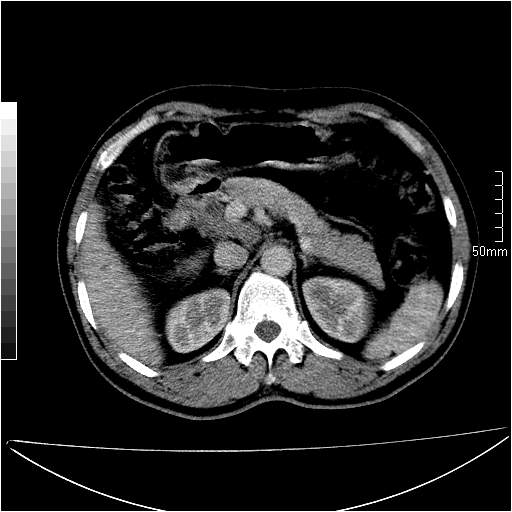

男性,54岁,皮肤黄染,搔痒一周余.b超示肝左叶回声异常.初步诊断1胆总管下段结石2胆囊结石伴慢性胆囊炎请各位战友帮忙看一下肝脏多发低密度如何解释恰当.增强效果不是很好.请大家见谅.

胆总管及肝内胆管扩张,考虑是结石!但,肝内的低密度区增强不明,可能是肝ca,因为肝ca在增强时呈快进快出.另年胆总管扩张原因,可以考虑一下是不是,胆管ca.再次要考虑肝内的低密度是否为海绵状血管瘤所致!

首先,胆总管下端结石梗阻伴肝内胆管扩张可确定。

其次,增强动脉期肝静脉显影,肝实质密度不均。——此为右心功能不全引起肝淤血的表现。

另外,肝八段低密度占位,呈多灶性,考虑肝脓肿或肝癌可能,(图像质量欠佳)建议进一步检查。

由于胆囊窝内结构显示不清,肝脏病灶又邻近胆囊窝首先考虑胆囊癌肝受侵犯。而后因肝脏病灶强化有渐进改变,且相邻胆管扩张,故考虑肝胆管细胞癌待排。

左肝胆管细胞癌。

胆总管下端结石。